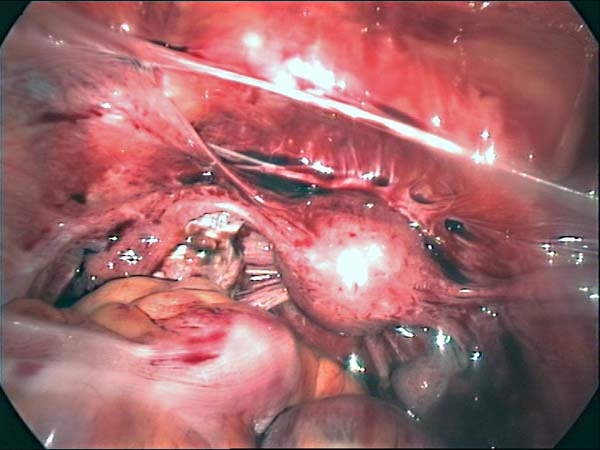

Photos laparoscopie Kyste ovarien Cystectomie ovarienne Septum utérin Grossesse tubaire